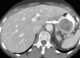

Gastrointestinal stromal tumor

Gastrointestinal stromal tumors (GISTs) are the most common mesenchymal neoplasms of the gastrointestinal tract. GISTs arise in the smooth muscle pacemaker interstitial cell of Cajal, or similar cells. [Source: Wikipedia ]